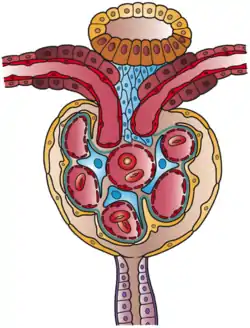

The renal corpuscle is the site of the filtration of blood plasma. The renal corpuscle consists of the glomerulus, and the glomerular capsule or Bowman's capsule.[3]: 1027

The renal corpuscle has two poles: a vascular pole and a tubular pole.[4]: 397 The arterioles from the renal circulation enter and leave the glomerulus at the vascular pole. The glomerular filtrate leaves the Bowman's capsule at the renal tubule at the urinary pole.

Glomerulus

The glomerulus is the network known as a tuft, of filtering capillaries located at the vascular pole of the renal corpuscle in Bowman's capsule. Each glomerulus receives its blood supply from an afferent arteriole of the renal circulation. The glomerular blood pressure provides the driving force for water and solutes to be filtered out of the blood plasma, and into the interior of Bowman's capsule, called Bowman's space.

Only about a fifth of the plasma is filtered in the glomerulus. The rest passes into an efferent arteriole. The diameter of the efferent arteriole is smaller than that of the afferent, and this difference increases the hydrostatic pressure in the glomerulus.

Bowman's capsule

The Bowman's capsule, also called the glomerular capsule, surrounds the glomerulus. It is composed of a visceral inner layer formed by specialized cells called podocytes, and a parietal outer layer composed of simple squamous epithelium. Fluids from blood in the glomerulus are ultrafiltered through several layers, resulting in what is known as the filtrate.

The filtrate next moves to the renal tubule, where it is further processed to form urine. The different stages of this fluid are collectively known as the tubular fluid.

Glomerulus is red; Bowman's capsule is white.

Glomerulus is red; Bowman's capsule is white. Kidney tissue

Kidney tissue Glomerulus

Glomerulus This image shows the types of cells present in the glomerulus part of a kidney nephron. Podocytes, Endothelial cells, and Glomerular mesangial cell are present.

This image shows the types of cells present in the glomerulus part of a kidney nephron. Podocytes, Endothelial cells, and Glomerular mesangial cell are present.